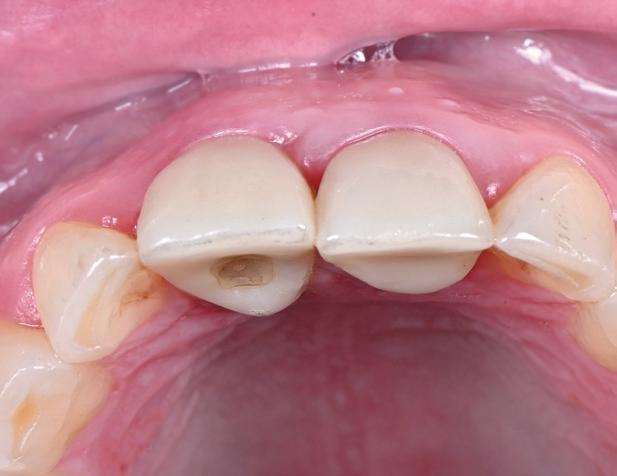

Posibilitatea ca nuanța gri să transpară prin gingie este un posibil dezavantaj al implanturilor de titan. În schimb, datorită culorii albe a dioxidului de zirconiu, această problemă estetică poate fi evitată prin

utilizarea implanturilor ceramice. Desigur, obținerea unei estetici excelente cu implanturile de titan este posibilă în mod curent. Cu toate acestea, o condiție prealabilă pentru un astfel de rezultat este prezența unei mucoase periimplantare cu o grosime de cel puțin 2 mm, care poate împiedica transparența cenușie a titanului. În lipsa acestei grosimi, mucoasa poate fi dublată de o grefă de țesut conjunctiv (recoltată de obicei din palat), necesitând însă o procedură chirurgicală adițională și, prin urmare, o povară suplimentară pentru pacient. Utilizarea bonturilor implantare integral ceramice este o soluție alternativă, dar microdeplasările bontului dur de dioxid de zirconiu pe implantul de titan mai moale pot duce la abraziune și chiar la distrugerea conexiunii implant-bont.

Totuși, ca și în cazul implanturilor de titan, în rare cazuri, și la cele ceramice poate apărea o recesie nedorită cu expunerea umărului implantar. Cu toate acestea, din punct de vedere estetic, această recesie a gingiei inflamate este posibil să fie mult mai bine tolerată de către pacienții preocupați de marginile întunecate ale implanturilor de titan (fig. 2).

În plus, aceste proprietăți bioinerte par să aibă și beneficii în ceea ce privește dezvoltarea periimplantitei și calitatea țesuturilor moi. În comparație cu titanul, dioxidul de zirconiu prezintă acumulare de placă și aderență bacteriană mai redusă, precum și o grosime mai mică a biofilmului depus. Și fluxul sanguin circulant către țesuturile moi este mai asemănător cu cel al unui dinte natural în cazul ceramicii față de titan, care oferă flux sanguin redus semnificativ. Se știe că o circulație sanguină mai bună înseamnă țesuturi moi mai sănătoase, care, la rândul lor, prezintă rezultate estetice îmbunătățite. Deși deocamdată lipsesc dovezile pe termen lung pentru implanturile ceramice, sunt disponibile rezultatele inițiale la 3 și 5 ani, iar tendința, susținută de studii preclinice și experiența clinică, este că dioxidul de zirconiu demonstrează același rezultat - iar în unele studii chiar o pierdere osoasă marginală mai redusă față de implanturile de titan. În această perioadă încă nu s-a descris clinic periimplantită.

Trebuie remarcat, totuși, că în cazul implanturilor ceramice, ca și în al celor de titan, cementita, adică inflamația periimplantară cauzată de reziduurile de ciment, poate duce la periimplantită. În plus, la implanturile din dioxid de zirconiu poate apărea supraîncălzirea la înșurubarea implantului în os, iar suprafețele excesiv de aspre sau poroase ale implantului pot cauza defecte osoase periimplantare din cauza termoconductivității reduse a materialului. Deși sunt necesare mai multe dovezi științifice care să demonstreze o tendință mai scăzută spre periimplantită în cazul implanturilor ceramice, argumentul esențial pentru aceste implanturi bazat pe experiența clinică este starea excelentă și aproape constant lipsită de inflamație a țesuturilor moi periimplantare (fig. 3).